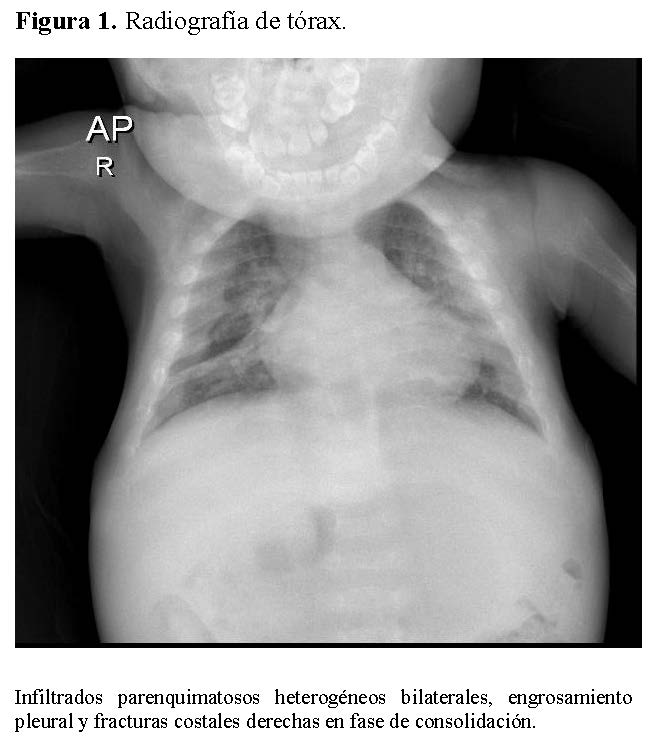

Chest radiography showed bilateral heterogeneous parenchymal infiltrates, pleural thickening, and right-sided rib fractures in the consolidation phase (Figure 1). Radiographs of long bones revealed severe osteopenia, periosteal reaction, and multiple pathological fractures, including the right and left humerus, right ulna, and right femur (Figures 2 and 3).